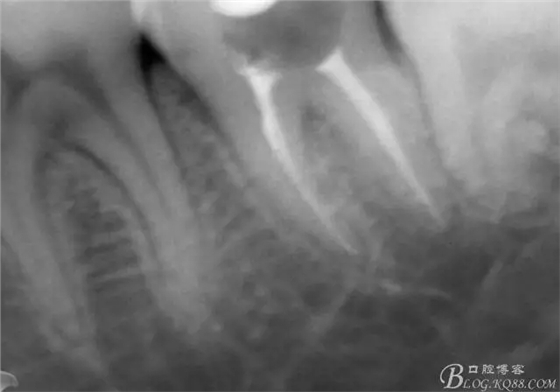

一周后復診,37叩(—)。去除暫封物,沖洗,試主尖拍片。

X線示牙膠尖到達工作長度,故行AH-PLUSH糊劑配合卡瓦熱牙膠機運用連續(xù)波充法根充,暫封拍根尖片。